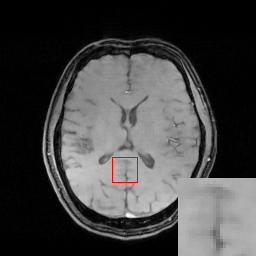

In the CS-MRI inversions, the zero-filled MR images usually serve as the starting point in the iterative optimization. Although the iterative de-aliasing can effectively remove the artifacts and achieve much more pleasing visual quality compared with zero-filled reconstruction, the distortion and information loss is inevitable in the reconstruction. To further illustrate this phenomenon, we compare the pixel-wise reconstruction errors among the zero-filling reconstruction and other reconstruction models of the MR image in Figure 2.

We take the difference between the absolute reconstruction error of zero-filled and the compared CS-MRI methods and only keep the nonnegative values, which can be formulated as

md=(|xfsx¯p||xfs𝒵(y)|)+.subscript𝑚𝑑subscriptsubscript𝑥𝑓𝑠subscript¯𝑥𝑝subscript𝑥𝑓𝑠𝒵𝑦m_{d}={\left({\left|{{x_{fs}}-{\overline{x}_{p}}}\right|-\left|{{x_{fs}}-{\cal Z}(y)}\right|}\right)_{+}}. (8)

Where the operator ()+subscript{\left(\cdot\right)_{+}} set the negative values to zero. We only keep the nonnegative values in the map, which results the filtered difference map. We show the corresponding filtered difference map mdsubscript𝑚𝑑m_{d} in figure 3 in the range [0 0.2]. The bright region means the better accuracy of zero-filled reconstruction. We observe the zero-filling reconstruction provide better reconstruction accuracy on some regions, indicating the information loss in the reconstruction occurs.

Figure 3: The filtered difference map d𝑑d between the reconstruction errors of the zero-filled reconstruction and recent CS-MRI inversions.

To alleviate the information loss in the guide module, we introduce the concatenation operation to utilize the information from both the zero-filled MR image and guidance image as the input to the error correction network. In later Experiment Section V, we further validate it by the ablation study.

To validate the architecture of the proposed DECN model, we conduct the ablation study by comparing the DECN framework with other Baseline network architectures in Figure 4, which we refer the model in Figure 4(a) as DECN with no input concatenation and error correction (DECN-NIC-NEC). With the guide module, a later cascaded CNN module learns the mapping from the pre-reconstructed MR image to the full-sampled MR image. Likewise, we name the models in Figure 4(b) (DECN-IC-NEC) and Figure 4(c) (DECN-NIC-EC). By comparing the DECN-NIC-NEC framework with the DECN-IC-NEC framework, we evaluate the benefit brought by the concatenating the zero-filled MR images and corresponding guide MR images as the input to compensate the information loss in the guide module. In Figure 3, we give the illustration the information from zero-filled MR images and guide images can be shared. By comparing the DECN-NIC-NEC framework with the DECN-NIC-EC framework, we evaluate how the error correction strategy improves the reconstruction accuracy compared with simple cascade manner.